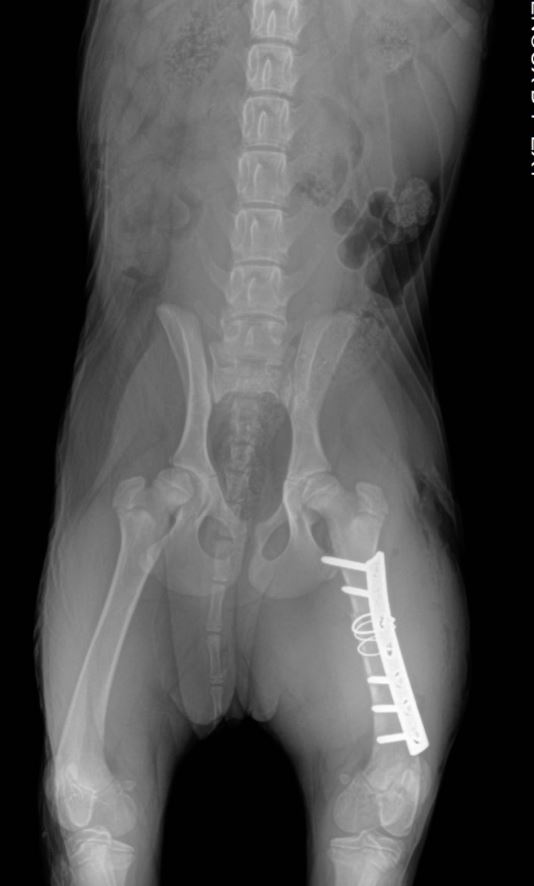

Chirurgies orthopediques:

-réduction des fractures (pose divers implants plaques broches etc),

Pose implant plaque DCP